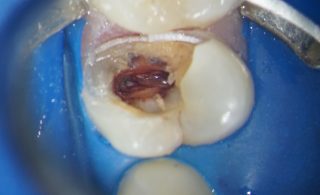

Va prezint un caz realizat impreuna cu colegul meu, Dr. Sergiu Spataru, medic specialist endodont. Dintele din imagine, un premolar cu o carie profunda si inflamatie ireversibila a nervului, a fost tratat endodontic. Se poate observa cum una din crestele marginala este complet desfiintata impreuna o buna parte din coroana dintelui (cuspidul palatinal).

Dupa ce caria a fost in intregime curatata, s-au refacut peretii si s-a realizat tratamentul endodontic, apoi dintele a fost pregatit pentru a primi o coroana partiana.